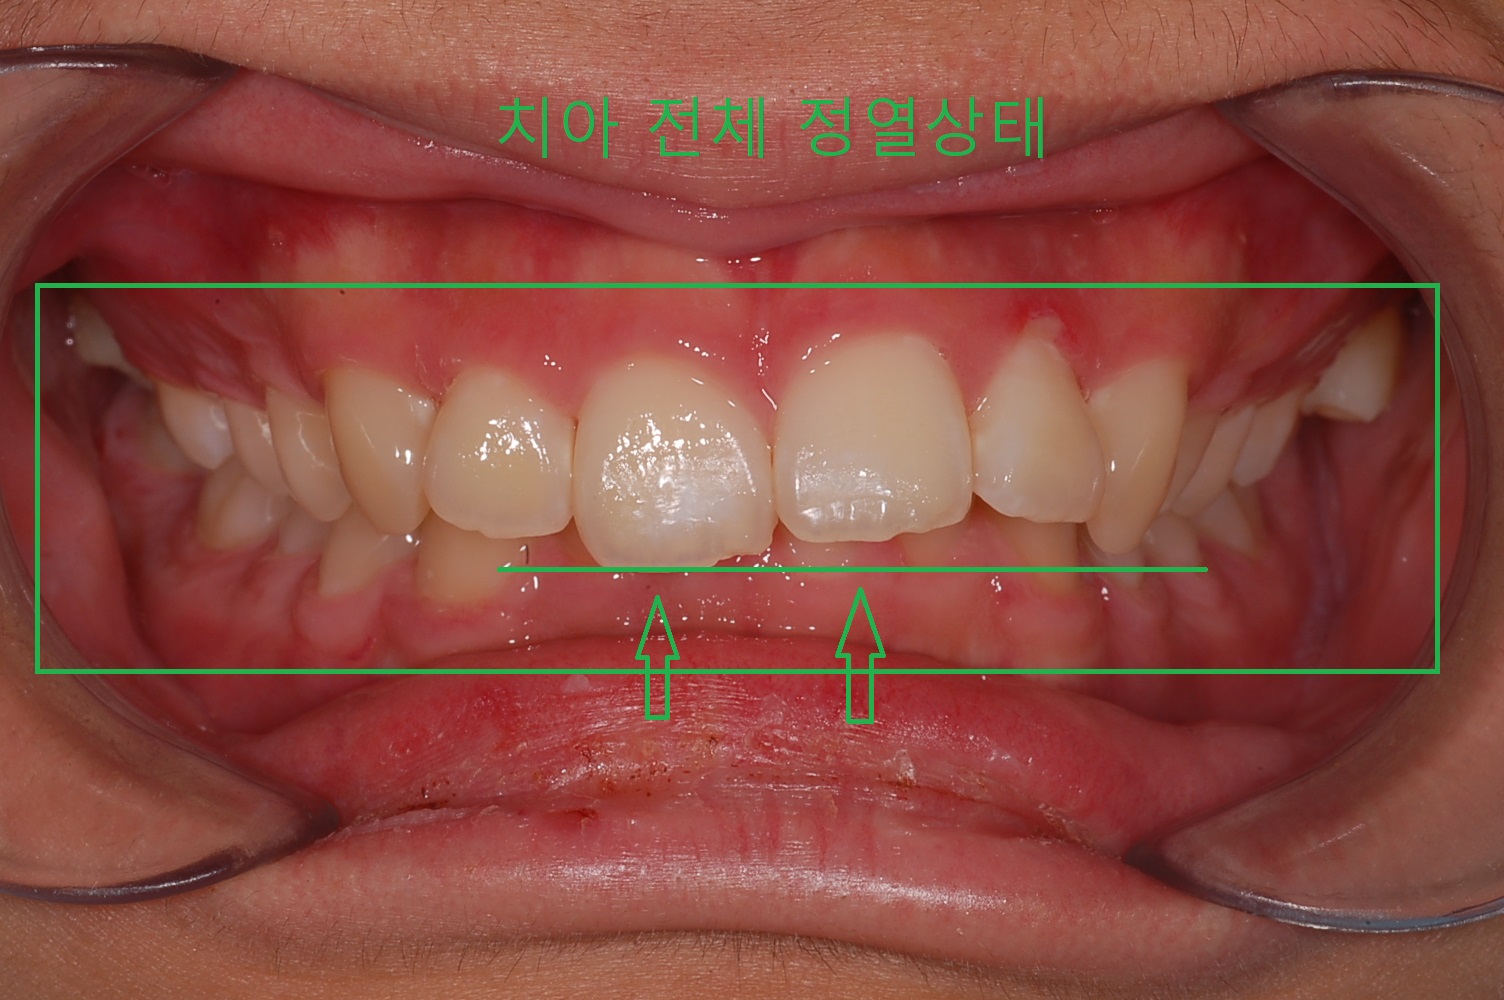

과개교합은 윗니가 아랫 니를 덮는 정도가 정상범위를 넘어갈 때 과개 교합이라고 합니다. 간단하게 말해서 윗니가 아랫니를 덮어버린다는 뜻입니다.

치아는 서로 잘 맞물려야 제 기능을 하게 되는데 과개교합이 길어질수록 아래치아가 마모가 심해지며 턱관절이 안 좋아질 수 있습니다.

◎ 아들치아교정 전 상태확인 (과개교합사진)

- 「윗 앞니 과개교합」

전체 교정 브라켓을 부착 후 2달 정도 지나고 나니 S자로 휘어진 철사가 어느 정도 일자로 복원되면서 앞니의 치아배열이 가지런하게 정리가 되어있습니다.